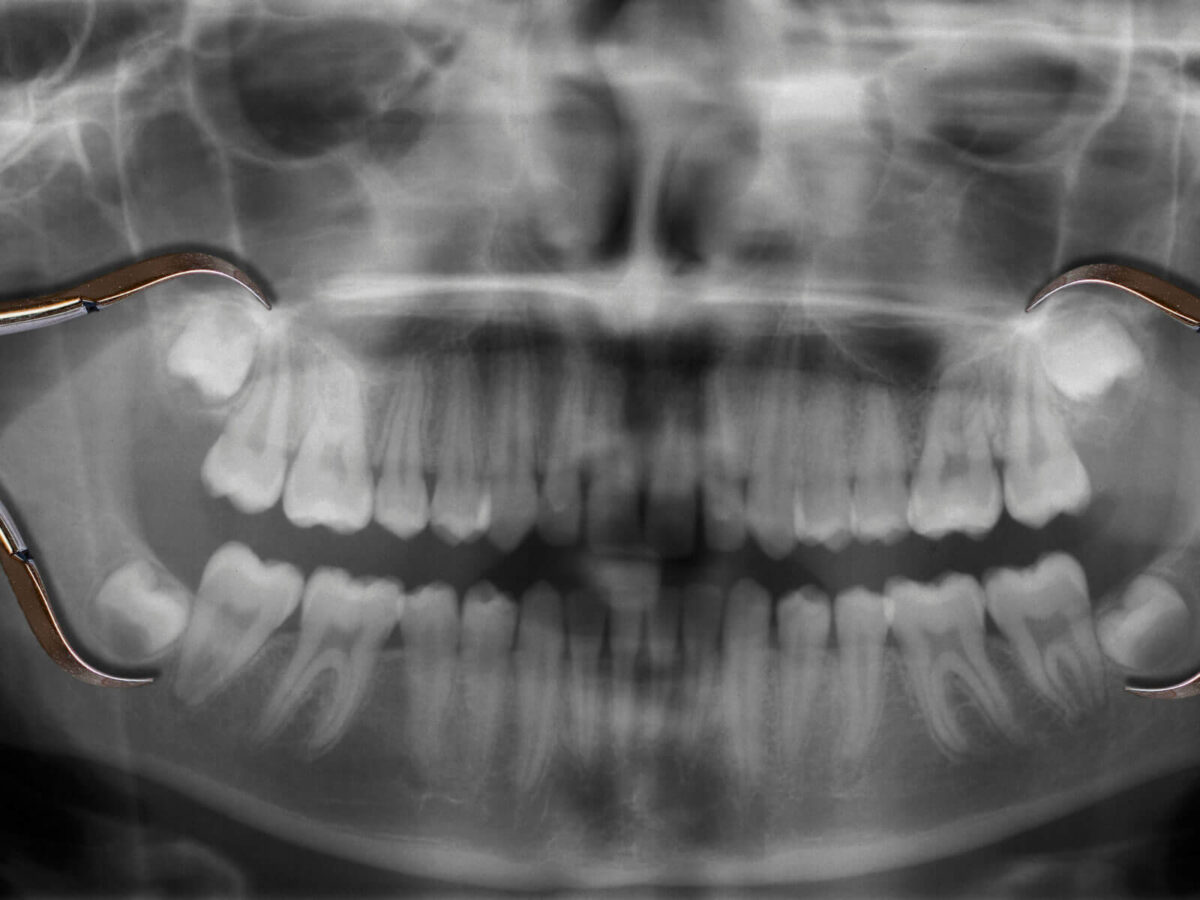

In general, they show up sometime between ages 17 and 25. The American Dental Association notes that third molars commonly erupt in late adolescence or the early adult years.[Reference] But the word “typically” does a lot of work there. Some people feel changes at 16. Others don’t notice anything until their mid-twenties. And a few barely notice at all.

According to the American Association of Oral and Maxillofacial Surgeons, around 90 per cent of people end up with at least one impacted wisdom tooth because space is limited. [Reference] Even before a tooth becomes fully impacted, that tight space alone can cause a sense of fullness. It doesn’t always become sharp pain. Sometimes it just hangs around in the background and won’t fully disappear.

The real issue isn’t just when wisdom teeth come in. It’s how they come in. Are they straight? Is there enough room? Are they easy to clean?

Position matters more than timing.